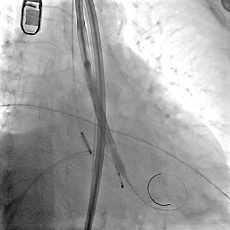

主动脉根部造影

TF29瓣膜,0位定位释放

瓣膜稳定释放至全展开